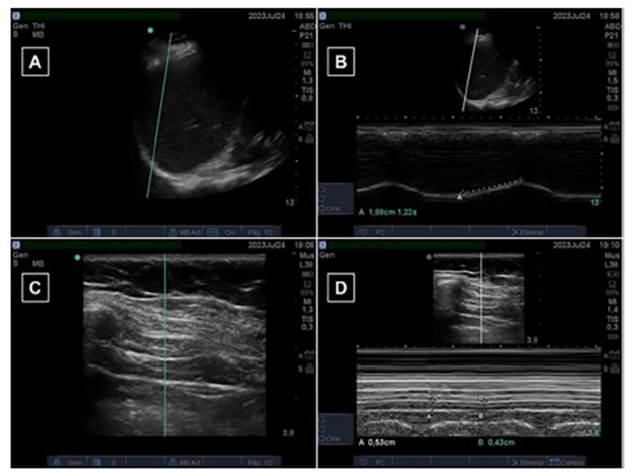

•

Función diafragmática: Se utilizó el ecógrafo portátil (Fujifilm© SonoSite M-Turbo) prestado por Tecnoimagen

S. A. con fines académicos durante la duración del trabajo. Las distintas

visiones ecográficas conseguidas en ambos modos (B y M) de las distintas

variables se ilustran en la Figura 2. En la medición de la ED, se

utilizó un transductor convexo de 5-1 MHz en modo-M localizado en la línea

axilar anterior entre la 8.va

y la 10.ma

costilla. La ED fue expresada en centímetros (cm). Para evaluar

la TFdi, se utilizó un transductor lineal de 5-10 MHz

en modo-M. La variable fue expresada en %, la cual fue calculada según la

siguiente ecuación:19